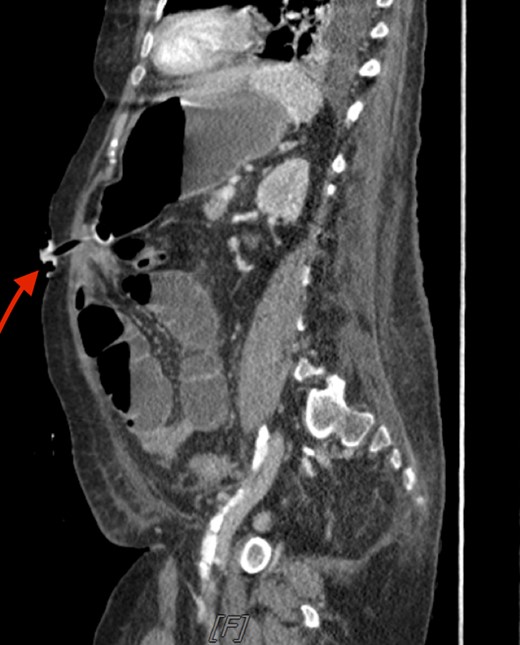

A critically ill 74-year-old female underwent tracheostomy and subsequent percutaneous endoscopic gastrostomy (PEG) tube placement. On the following day, after starting feeds through the PEG tube, the patient developed abdominal distention. An abdominal X-ray showed possible concern for a small bowel obstruction (SBO). A computed tomography (CT) scan further confirmed dilated small bowel loops proximally with distal collapse and transition point near the gastrostomy tube site. On sagittal view, the small bowel appeared entrapped between the abdominal wall and the stomach (Fig. 1). All feeds were stopped and the PEG tube was placed on gravity drainage to decompress the stomach and small bowel.

Sagittal CT scan of the abdomen. The arrow is pointing to the small bowel entrapped between the abdominal wall and stomach.